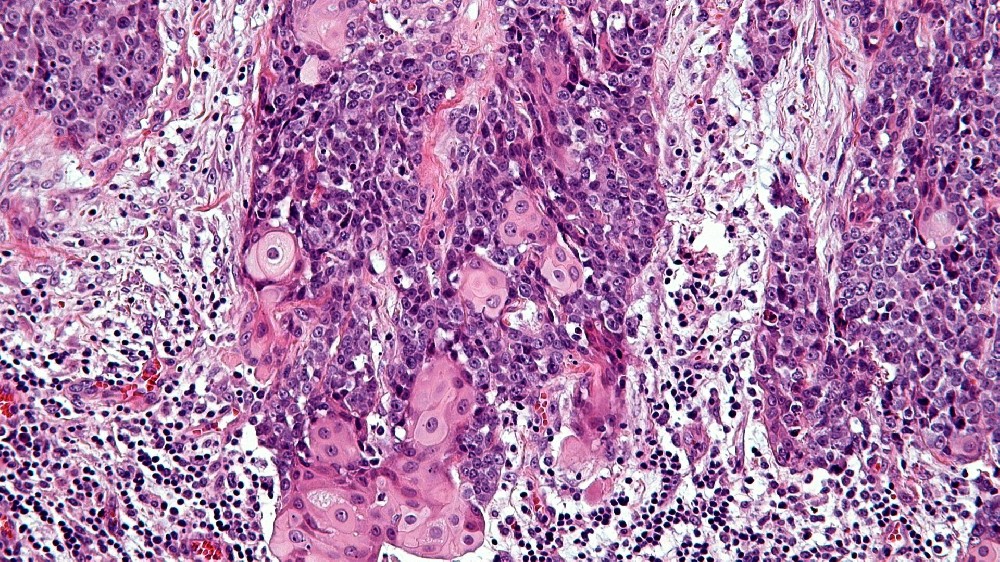

中線管癌 (NUT 癌症)是一種極為罕見但具侵略性的癌症,特徵為特定的基因突變。這種惡性腫瘤通常發生在身體的中線結構,如肺、縱膈、鼻腔或唾液腺,其特徵是位於 15 號染色體的睪丸核蛋白 (NUTM1) 基因重排。由此產生的基因改變會促進異常的細胞增殖和快速的腫瘤生長。

近年來,由 James P. Allison 教授和 Gregg Semenza 博士等知名諾貝爾獎得主所贊同的突破性研究,已闡明 NUT Carcinoma 的分子結構。這種癌症的表現主要是由於融合的染色體易位所致。 NUTM1 基因與 BRD4 或 BRD3 等基因,造成快速且無法控制的細胞分裂。

以涉及 NUT 基因的基因易位為標記。